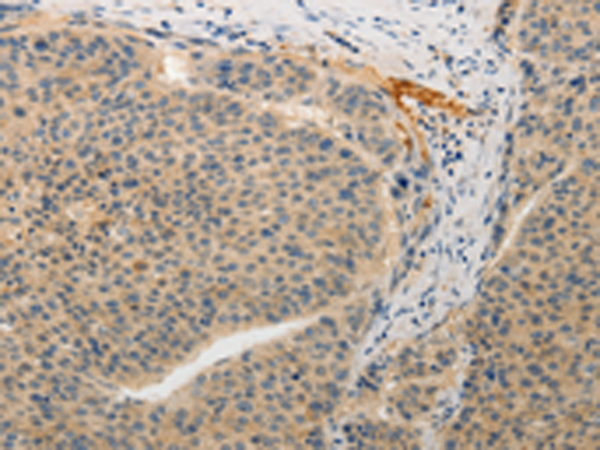

分类: 科研抗体货号: P11172别名:应用: IHC反应种属: Human, Mouse

分类: 科研抗体货号: P11170别名: PAQR2; ACDCR2应用: IHC反应种属: Human, Mouse

分类: 科研抗体货号: P11167别名: DSH; AGS6; G1P1; IFI4; P136; ADAR1; DRADA; DSRAD; IFI-4; K88DSRBP应用: IHC反应种属: Human

分类: 科研抗体货号: P11175别名:应用: IHC反应种属: Human

分类: 科研抗体货号: P11187别名: ANKRA应用: IHC反应种属: Human, Mouse

分类: 科研抗体货号: P11166别名: ADAM-TS6; ADAMTS-6; ADAM-TS 6应用: IHC反应种属: Human

分类: 科研抗体货号: P11174别名: AYTL3; AGPAT7; LPEAT2; LPAAT-eta应用: WB,IHC反应种属: Human, Mouse

分类: 科研抗体货号: P11186别名:应用: IHC反应种属: Human